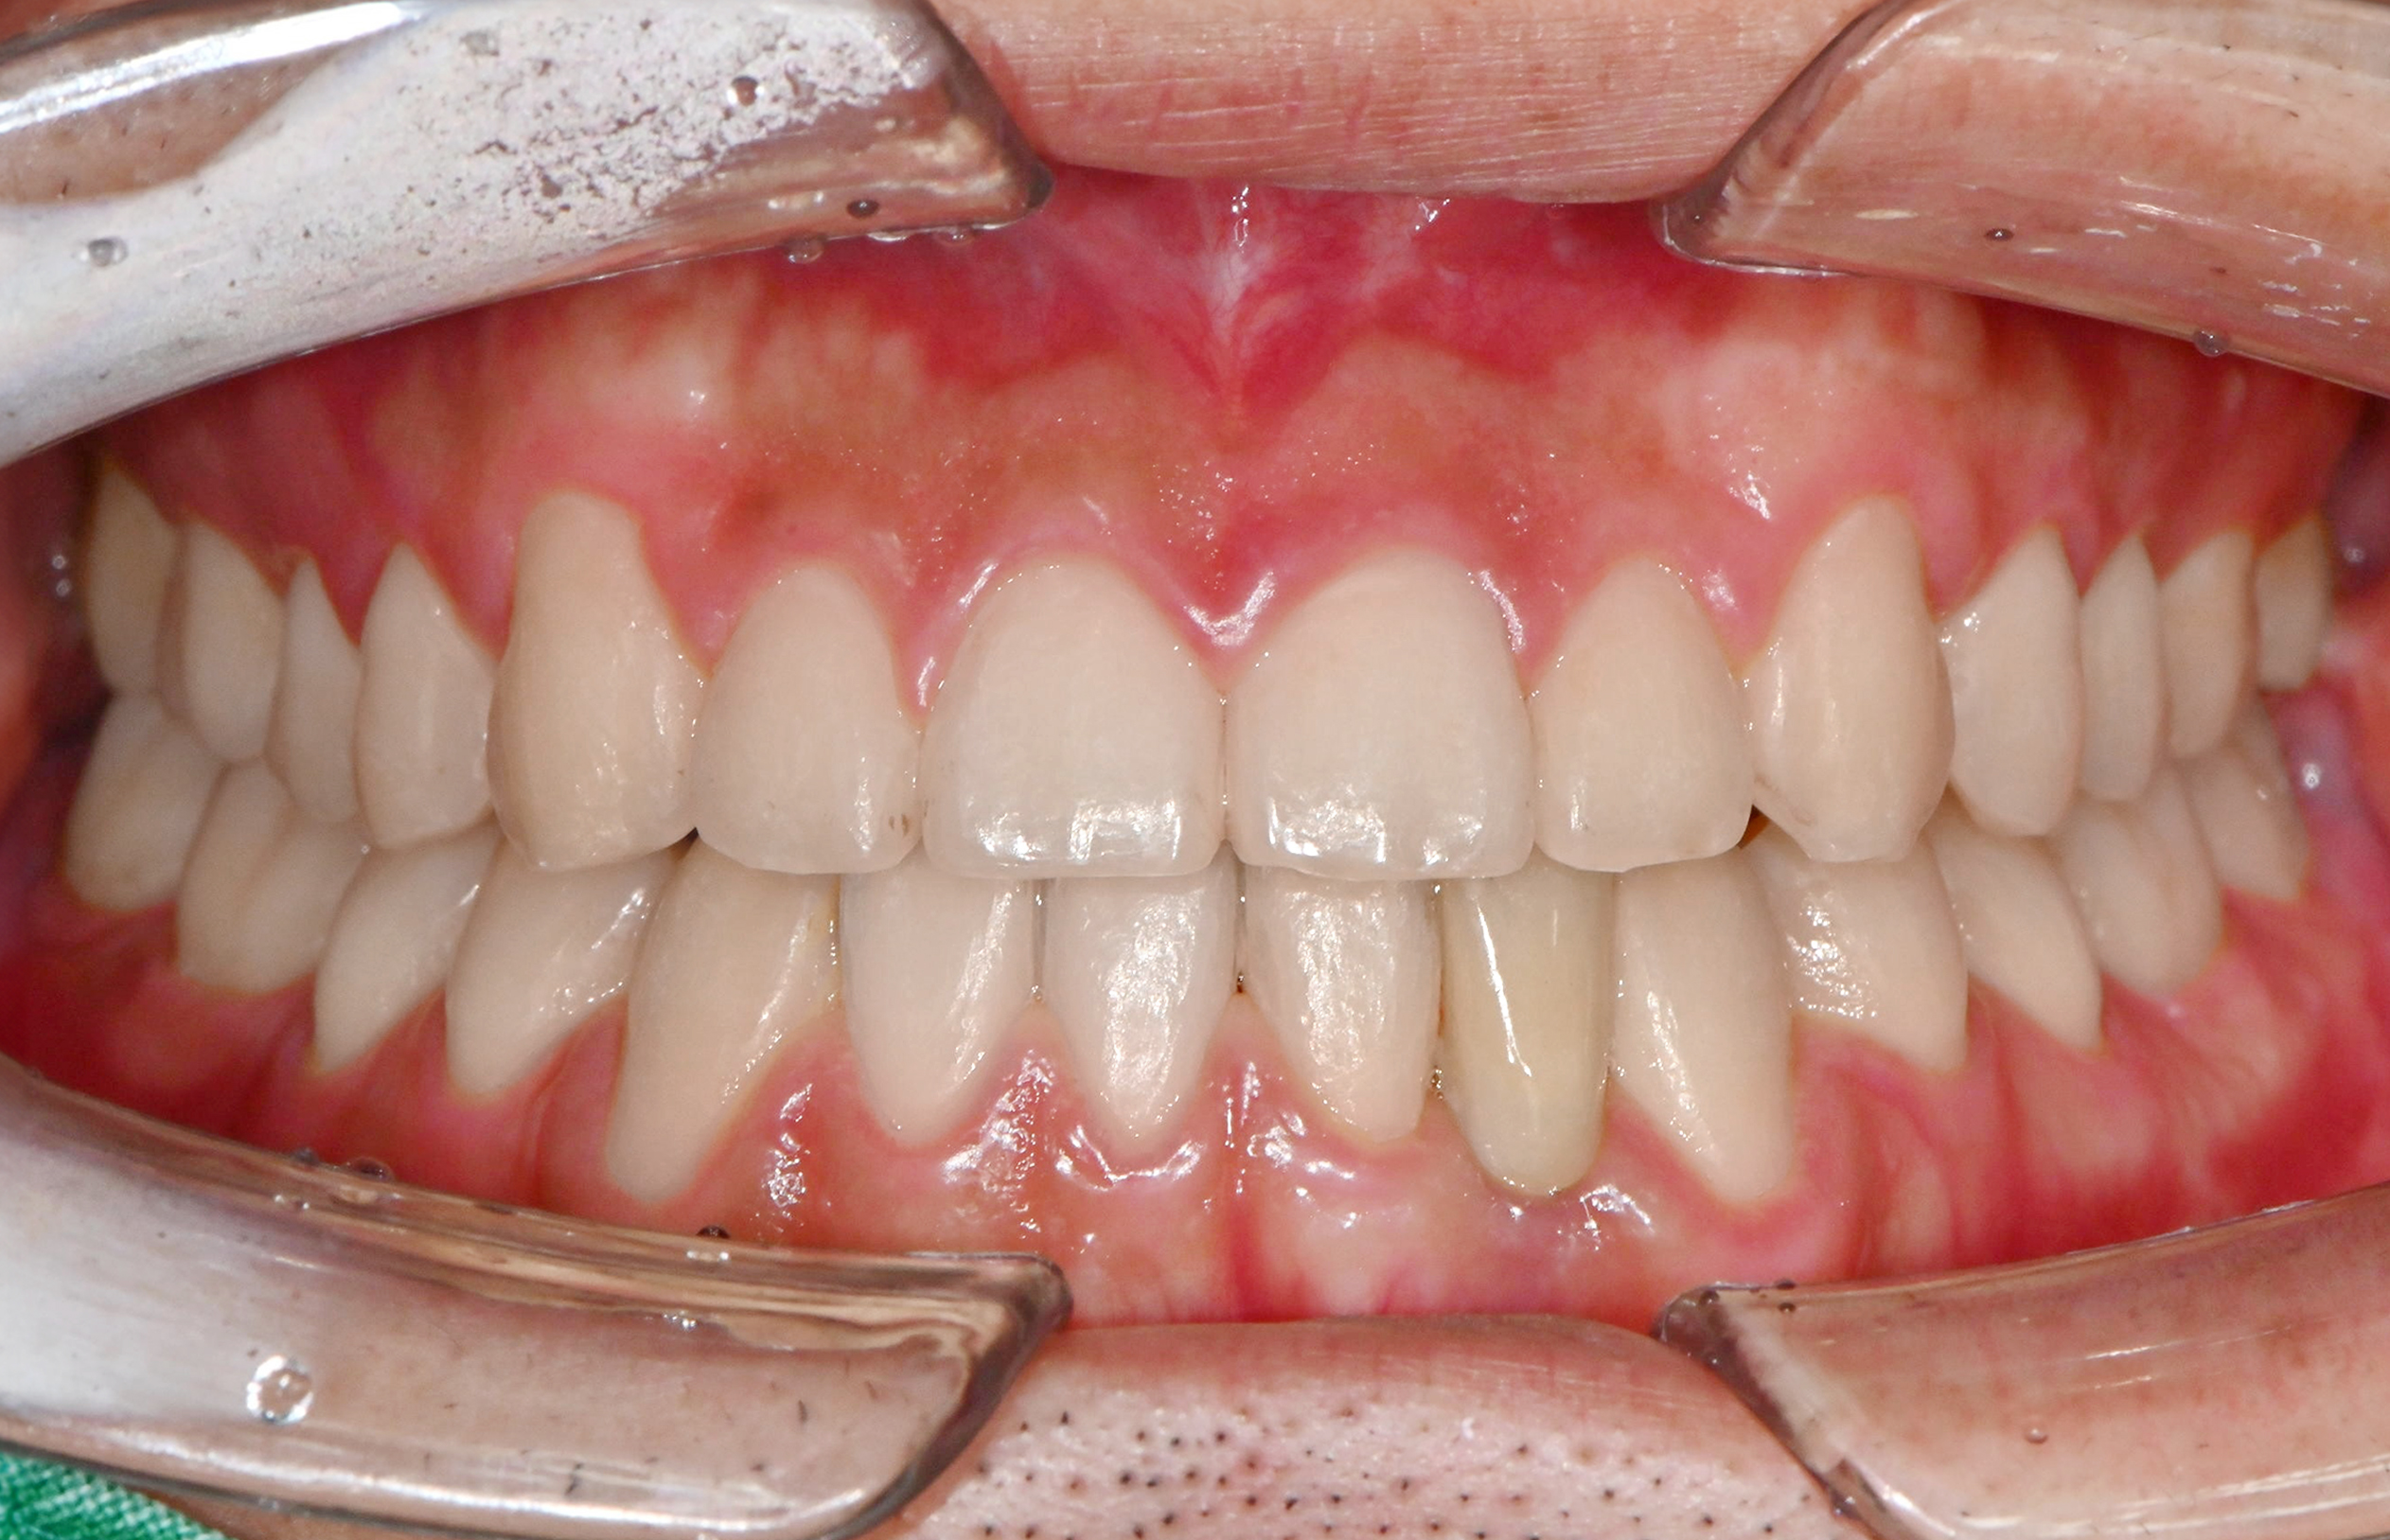

맞는 건 괜찮은데… 충치는 못 참겠습니다|20대 격투기 선수 치과 방문기